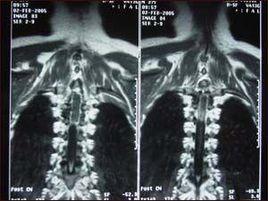

脊髓髓內腫瘤約占椎管內腫瘤的15%~20%,以發生於頸、胸段椎管者多見。髓內腫瘤中,主要為各類型的膠質瘤,少數為上皮樣囊腫、皮樣囊腫、血管網狀細胞瘤和脂肪瘤等,還可有轉移瘤和脊膜瘤。髓內腫瘤大都以感覺障礙為首發症狀,從外科治療的觀點來看,脊髓髓內腫瘤可以分成兩類,一類是質地軟的浸潤性腫瘤,如惡性星形細胞瘤、多形性膠質母細胞瘤,此類腫瘤呈浸潤性生長,常有液化、壞死和囊性變,與正常脊髓組織無明確界限,不可能完全切除;另一類的質地偏硬,與周圍的脊髓組織有清楚的分界,有可能全部切除,如室管膜瘤、血管網狀細胞瘤和星形細胞瘤1級(毛細胞型)等。

髓內腫瘤手術時,必須切開脊髓,將腫瘤與之分離,才能將腫瘤摘出。一般統計,髓內腫瘤發生於頸段脊髓者約占50%,術後因神經損傷和脊髓水腫可加重原已存在的症狀,甚或發生呼吸肌麻痹、中樞性高熱等併發症,故手術的危險性較大。如套用顯微外科技術,可將手術損傷性減輕到最低程度。

根據脊髓造影和MRI顯示的腫瘤長度,決定手術切口和椎板切除的數目。椎板切除後,可見病變部位的硬脊膜外脂肪大部消失,硬脊膜囊呈梭形膨大,觸之有堅實感,在膨大的上方可見到搏動,而下方則搏動消失。椎板切除務必超過此腫大區域,至呈現正常硬脊膜外脂肪為度。

在硬脊膜上兩側各縫合數針牽引線後,將硬脊膜在脊髓的膨脹部做中線切開。需注意的是,有時脊髓可與硬脊膜粘連,故切開硬脊膜時先在瘤周無粘連處切開一小口,然後伸入顯微剝離子探查,有粘連則邊分離邊切或,著力點應偏向硬脊膜一側,不宜做硬脊膜的一次性切開,因為這樣做可能造成脊髓損傷。髓內腫瘤所在的脊髓節段呈梭形膨大,脊髓表面常看不到腫瘤,但可呈淡黃色或褐紫色,脊髓表面的血管多少不定。有時位於脊髓腹側的髓外腫瘤可使脊髓向背側隆起,而被誤認為髓內腫瘤。尤其是未做MRI檢查者,故在對脊髓做診斷性穿刺前必須細緻探查,排除此種可能性,再行穿刺為妥。